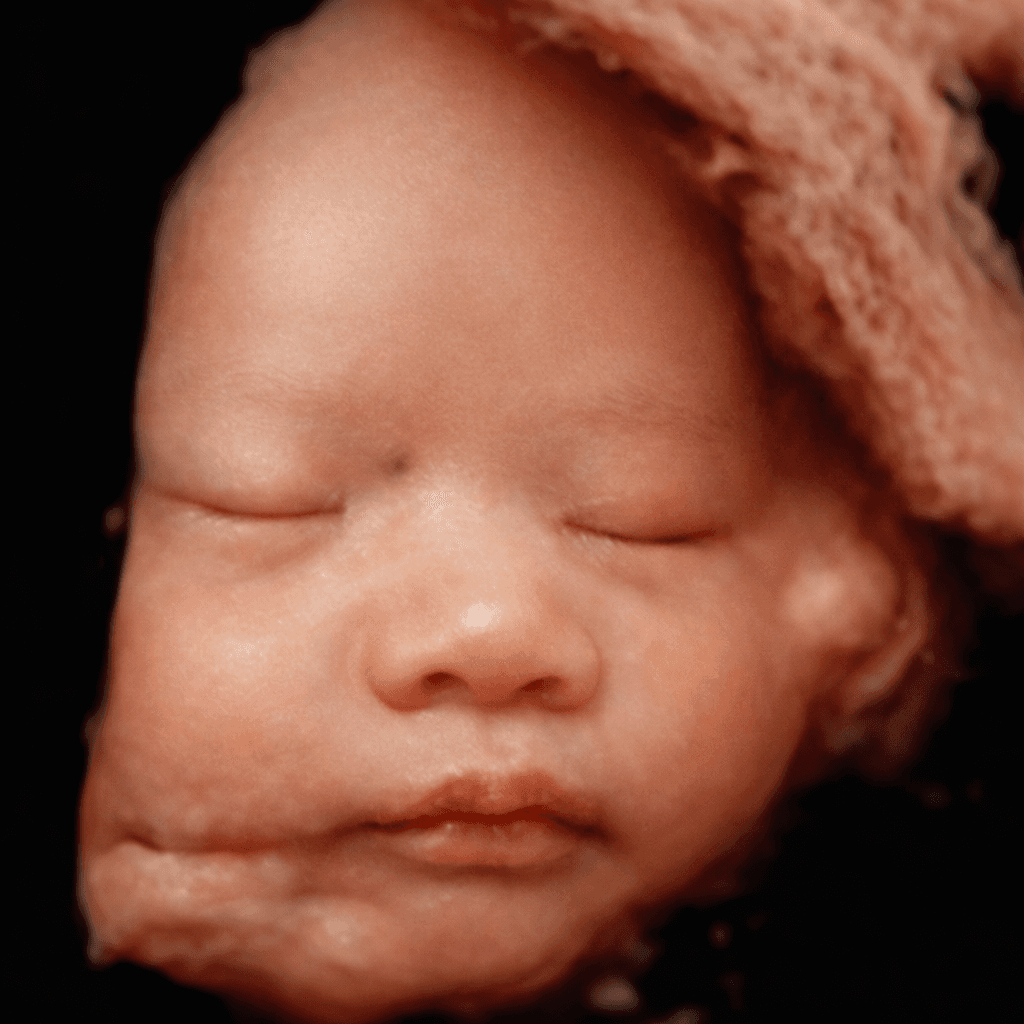

Công nghệ AI của LovelyBaby phân tích cấu trúc xương, làm rõ nét từng đường nét chân thực nhất trên khuôn mặt bé để tạo nên bức ảnh kỷ niệm tuyệt đẹp theo bạn suốt đời.

Tải ảnh Full HD về máy và chia sẻ niềm vui cùng gia đình.

Điều kì diệu đang ở ngay trước mắt,

ngắm nhìn thiên thần nhỏ ngay hôm nay